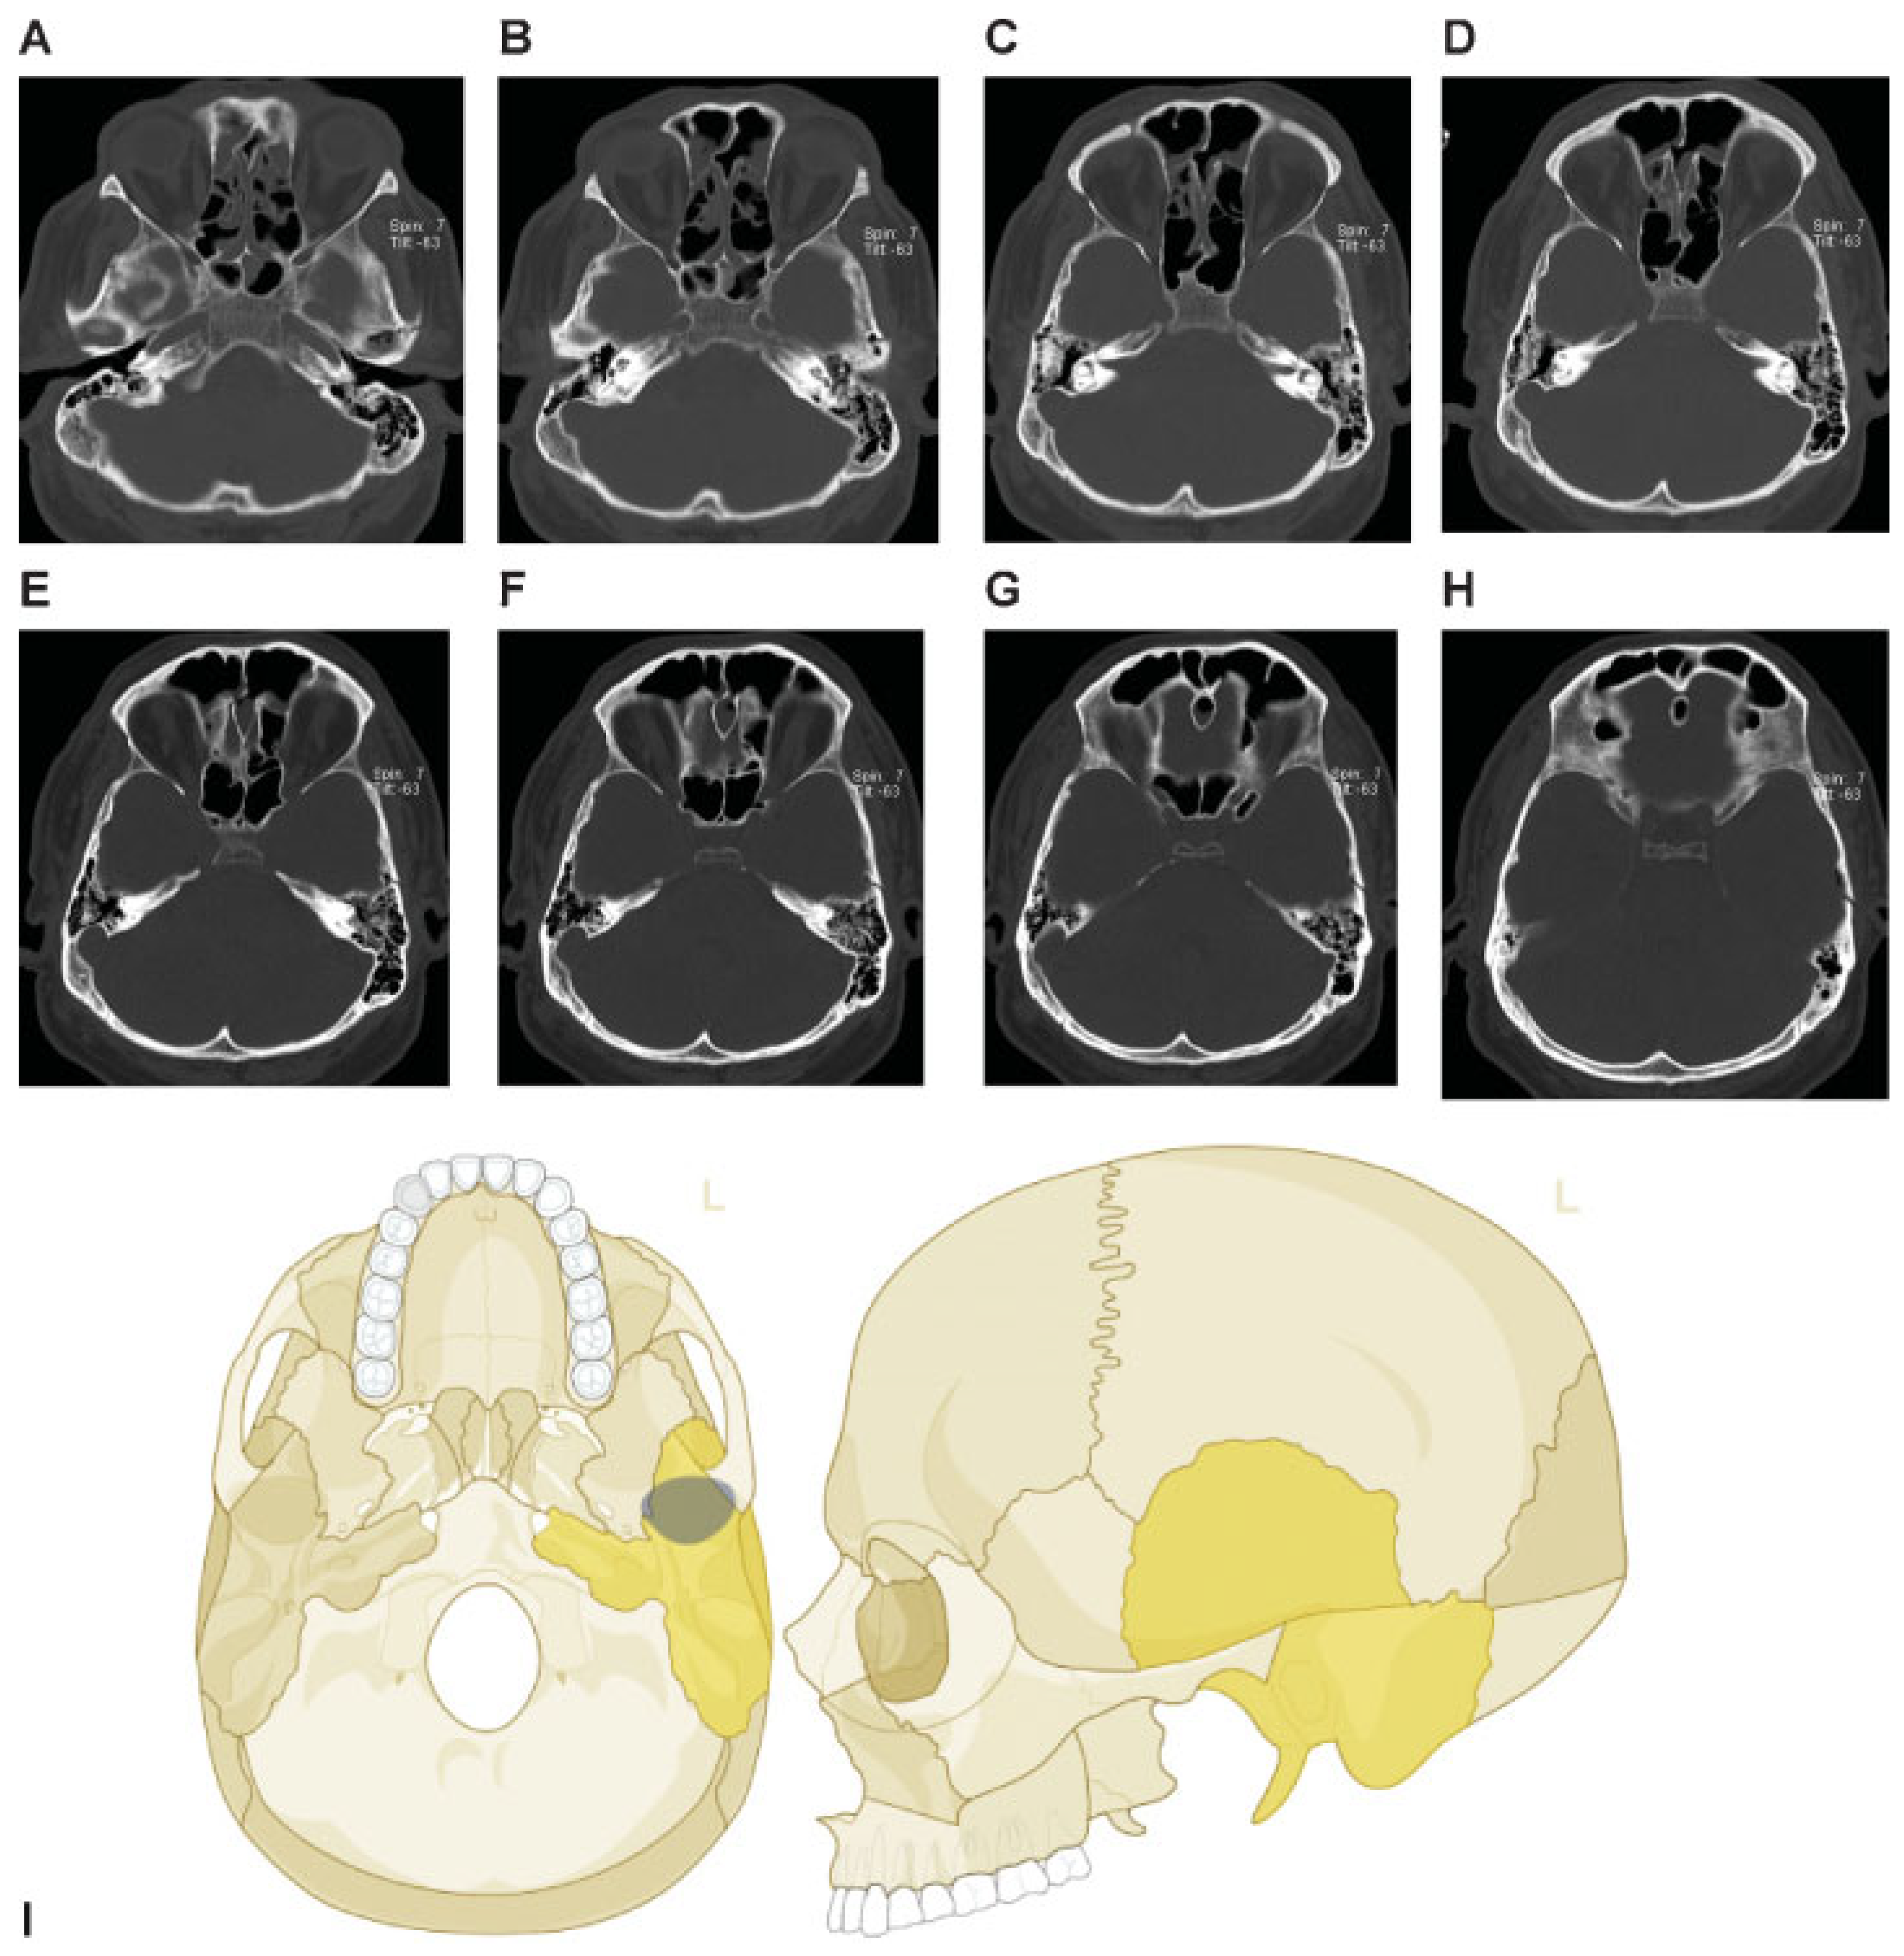

This coding system allows description of most relevant fracture patterns as illustrated in the case examples, such as the differentiation between unilateral or bilateral fracture patterns. In a series of three case examples, we illustrate the coding of a case with multiple cranial vault fractures (Figure 5), a single skull base fracture extending into the temporal cranial vault (Figure 6) and a right occipital and temporal cranial vault fracture extending into right middle fossa skull base (Figure 7). A range of additional fracture patterns are presented in a special case appendix as electronic supplement to this issue of the Journal (www.aocmf.org/classification).

Figure 5. Multiple cranial vault fractures. (A–F) Multiple cranial vault fractures. The right sided fractures involve the frontal and parietal vault with comminution and depression and extension inferiorly into the temporal cranial vault. Similarly, on the left, there is a linear parietal vault fracture that appears to continue into the temporal bone. (G) There is extension of these fractures into the left and right sphenoid bone. Imaging: Computed tomographic axial views. (H) Level 3 code: 93 S0.m.S0, 94 F1.P1.T0.m.T0.P0, This case example CMTR-93-94-001 is made available electronically for viewing using the AOCOIAC software at www.aocmf.org/classification.